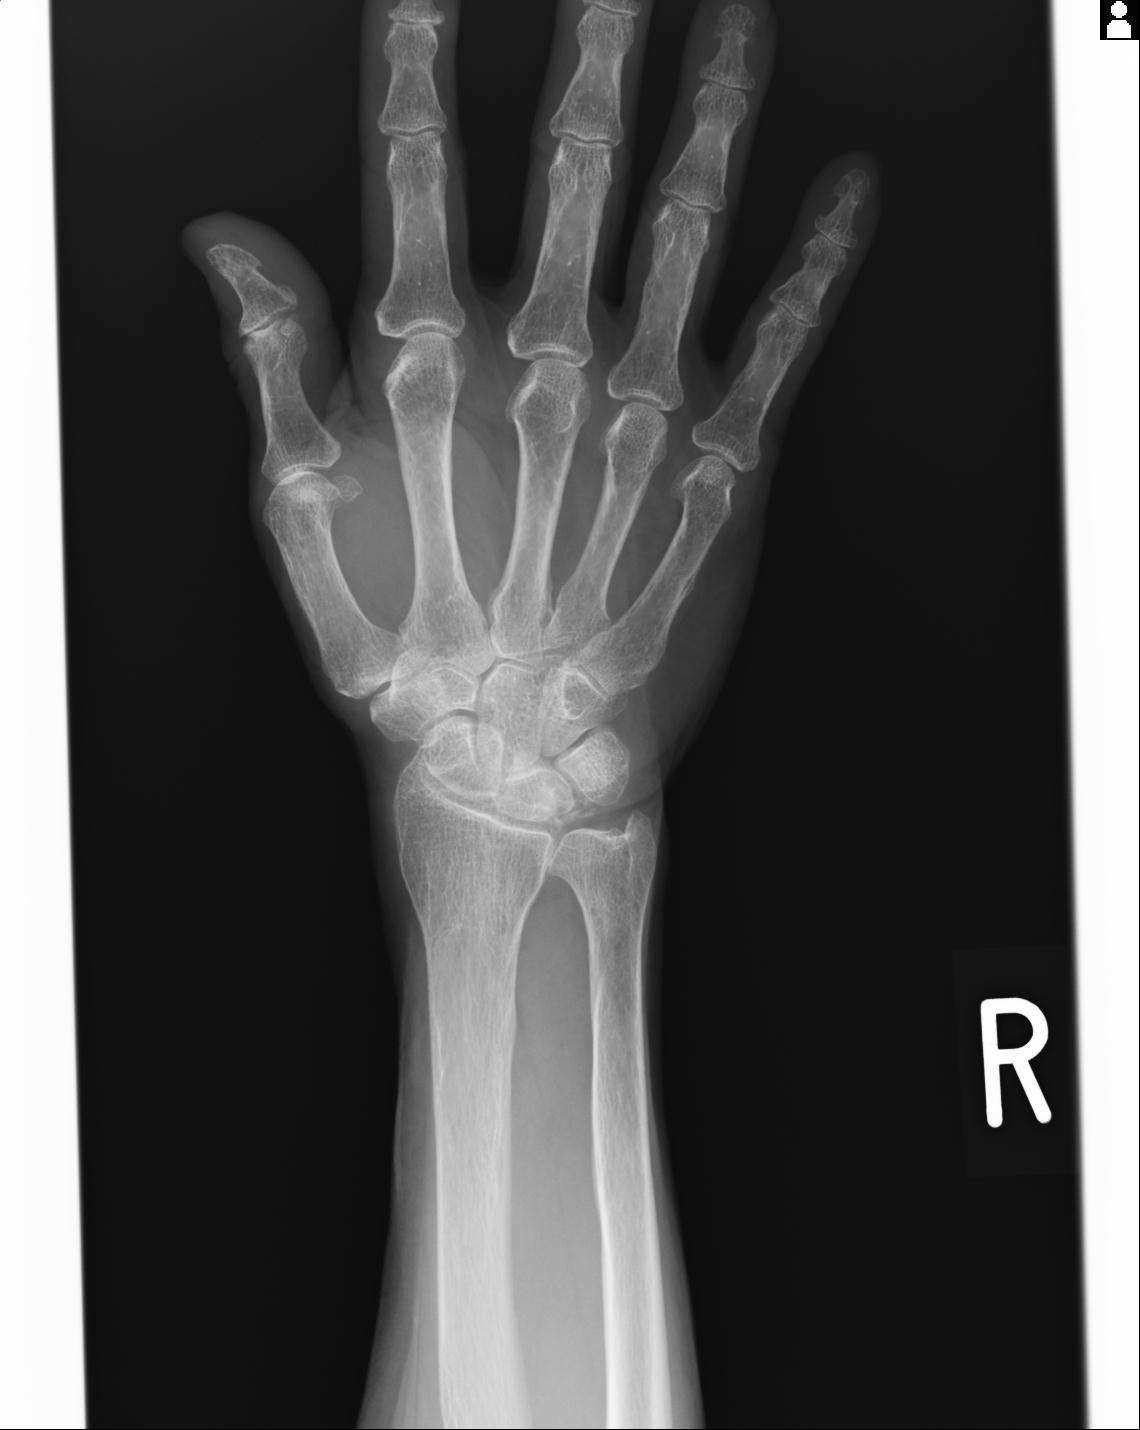

46666 1/23 両股正面+軸と右手関節 2R 76歳女性 右橈骨遠位端